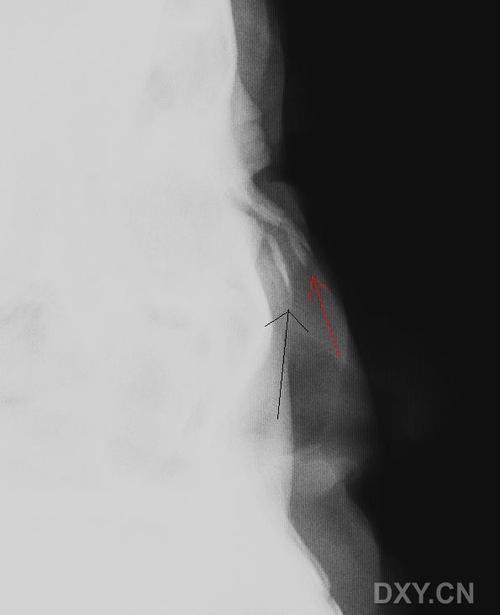

男,24岁,鼻部被击伤,如图所示,最可能的诊断是()

【请教】鼻骨外伤x线侧位片